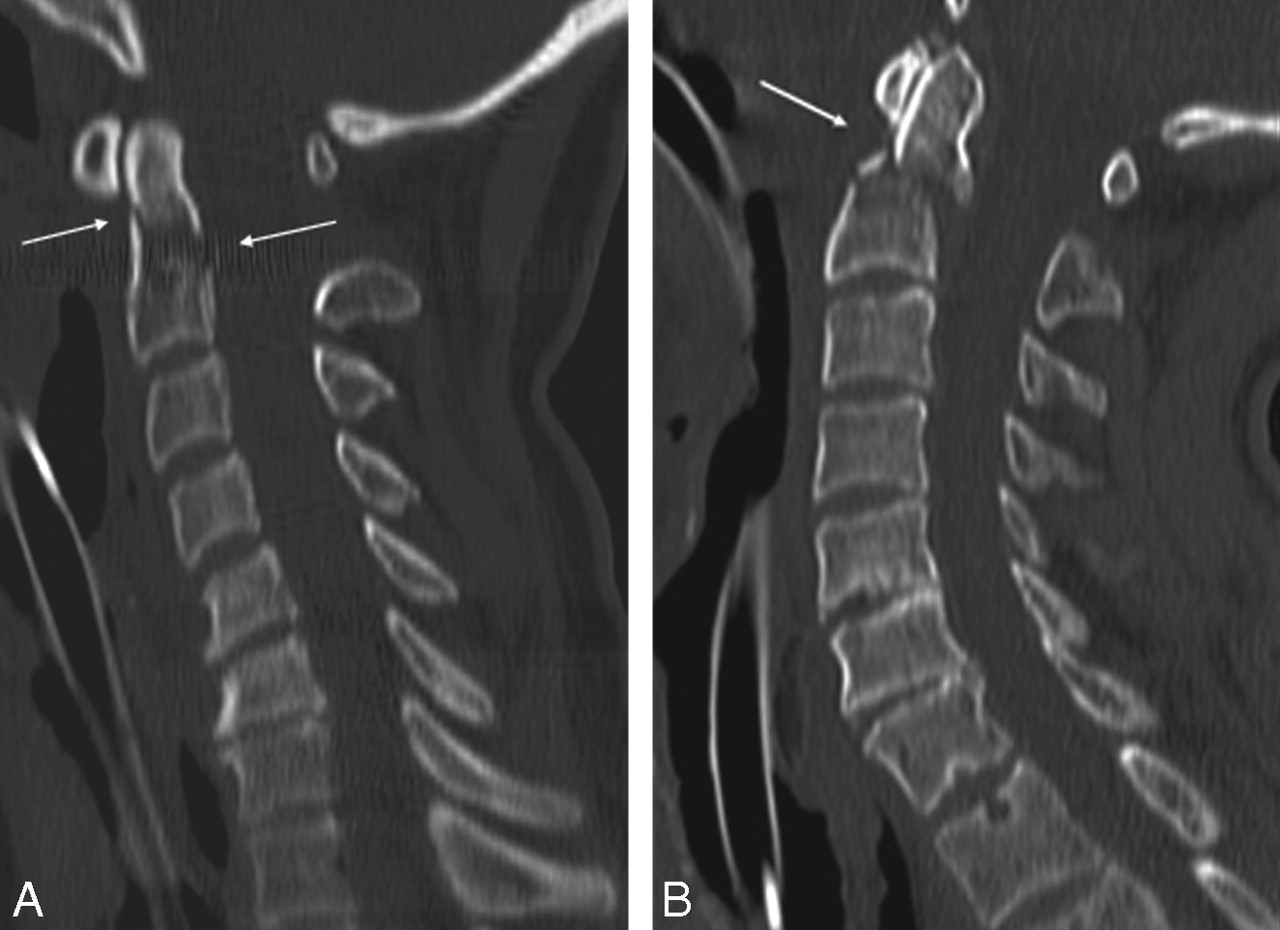

Of 191 patients, MDCT showed 18 patients with fracture(s) (9.4%), 3 in the standard-dose examinations and 15 in the low-dose examinations, with 4 fractures in the high-kilovolt group and 11 in the low-kilovolt group. Of these 18 fractures, 14 were unstable fractures (77.7%). Most fractures were situated at the C1–C2 level (n = 12): a large number of fractures at the base of the dens axis alone (n = 4; Fig 1) or in combination with other fractures (n = 2) at the level of C1 or C2 (Fig 2); 3 bilateral fractures of the arcus of C1 and/or C2; 2 pathologic fractures at the level of C2 (Fig 3); and 1 Hangman fracture. Two patients had an unstable burst fracture of a vertebral body (Fig 4). In 3 fractures, there was associated subluxation. Stable fractures were fractures of a spinous (n = 2; Fig 5 or of a lateral process (n = 2). The 2 experienced radiologists (R1 and R2) correctly identified all of the fractures in the first image interpretation at the moment of the presentation of the patient. The resident with 1 year of experience in CT (R3) also correctly identified all of the fractures. The first-year resident with no CT experience (R4) missed 3 fractures: 1 unstable fracture at the base of the dens axis (C2) and 2 stable fractures, 1 of a spinous and 1 of a transverse process. In 4 patients, standard radiography of the cervical spine at the moment of the presentation of the patient was interpreted as negative, whereby MDCT clearly depicted a fracture, 2 of them unstable fractures at the base of the dens axis (Fig 6).

A, A 53-year-old woman after polytrauma. Sagittal 2.50 mm image of standard-dose 16-MDCT examination (120 kV and fixed 250 mAs) shows fracture at the base of the dens of C2 (arrow). Calculated effective at examination is 3.9 mSv. B, A 62-year-old man after polytrauma. Sagittal 2.5-mm image of low-dose 16-MDCT examination (100 kV and 141 mAs, after tube current modulation) shows fracture at the base of the dens of C2 (arrow). Calculated effective dose is 1.4 mSv.